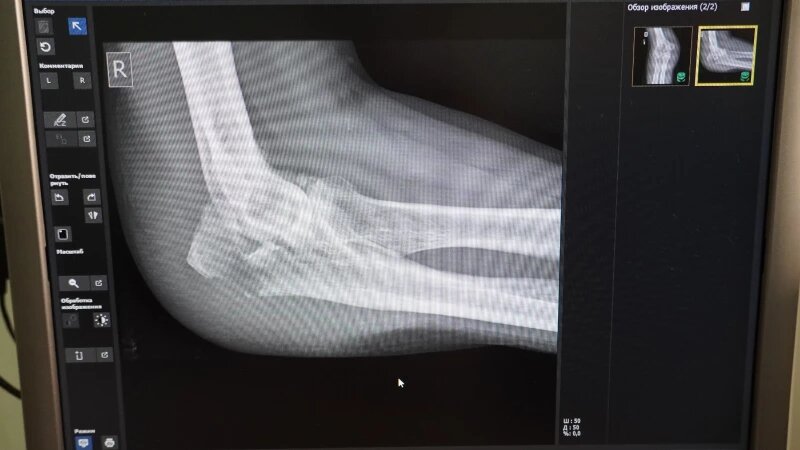

Самые уязвимые части тела в период гололедицы — это нижние и верхние конечности, говорит Константин Карапыш. Первыми под удар попадают нижняя треть предплечья и лодыжки — область голеностопного сустава.

Это связано с тем, что, поскользнувшись, человек рефлекторно выставляет руку вперед и падает на нее всем своим весом. Отсюда самая распространенная травма — перелом дистального метаэпифиза лучевой кости.

Лодыжку же человек повреждает, поскользнувшись на каком-нибудь бугристом месте. Нога подворачивается внутрь или наружу — связки испытывают сверхнатяжение, из-за чего кость буквально лопается.

«Так делать точно не стоит. Если вы получили травму, то стоит как можно скорее обратиться в травмпункт. Там сделают рентген-снимок, и после этого врач точно скажет, ушиб это или серьезный перелом, а после назначит лечение», — предупреждает травматолог.

От вида и степени травмы будет зависеть лечение и время восстановления. Так, поврежденная лодыжка без смещения будет заживать шесть недель. А при оскольчатом переломе человеку может потребоваться оперативное вмешательство и долгая реабилитация.